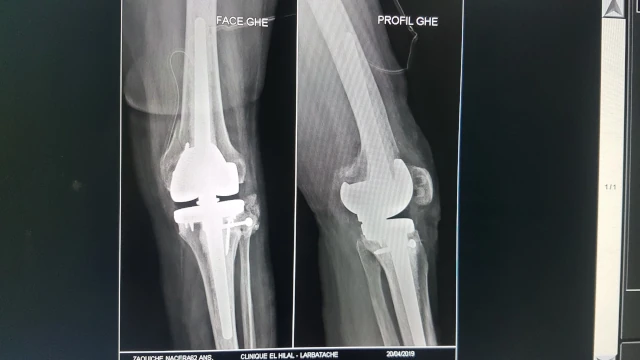

Remplacement de l'articulation du genou par prothèse tricompartimentaire sur une déformation inférieure ou égale à 10° dans le plan frontal

Remplacement de l'articulation du genou par prothèse tricompartimentaire sur une déformation supérieure à 10° dans le plan frontal

Remplacement de l'articulation du genou par prothèse unicompartimentaire fémorotibiale ou fémoropatellaire